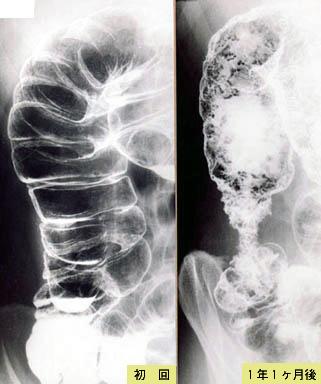

경과관찰 중에 대장의 악성 림프종이 합병된 궤양성 대장염

염증성 및 궤양성질환/궤양성대장염

대장/상행

X-P